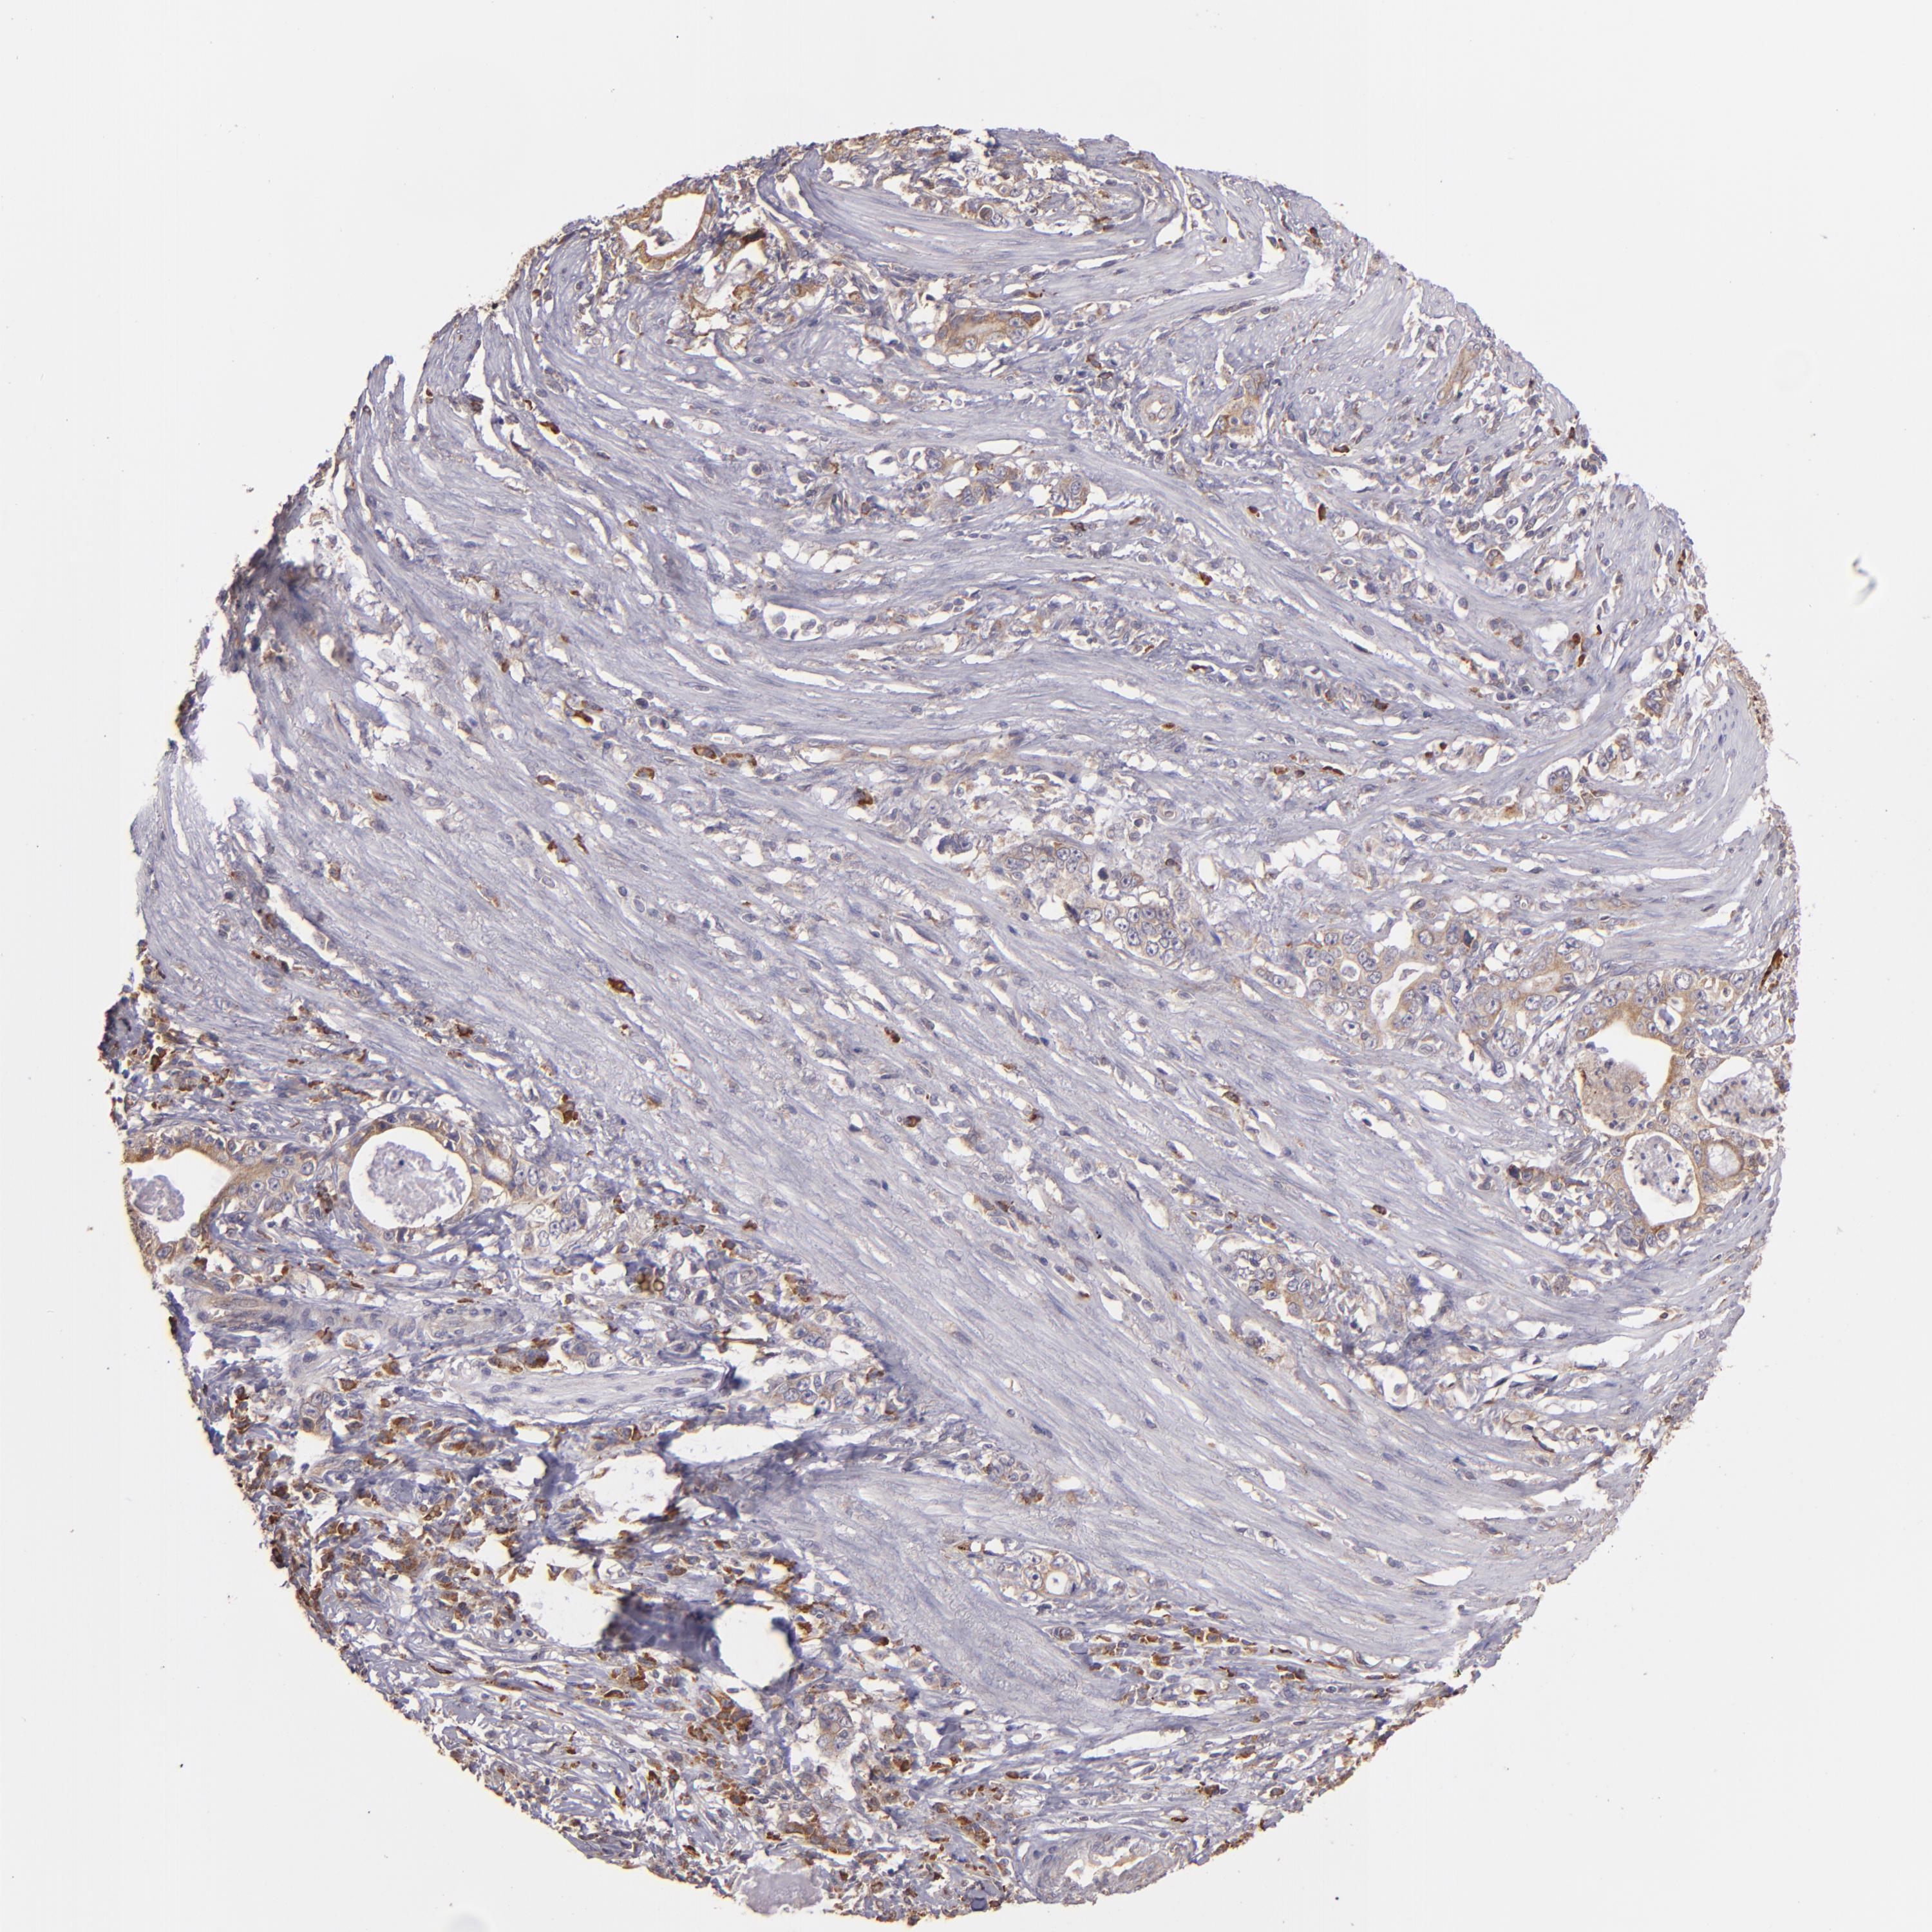

STOMACH CANCER - Protein expressioni

A mouse-over function shows sample information and annotation data. Click on an image to view it in a full screen mode. Samples can be filtered based on level of antibody staining by selecting one or several of the following categories: high, medium, low and not detected. The assay and annotation is described here.

Note that samples used for immunohistochemistry by the Human Protein Atlas do not correspond to samples in the TCGA dataset.

Antibody stainingi

Antibody staining in the annotated cell types in the current human tissue is reported as not detected, low, medium, or high, based on conventional immunohistochemistry profiling in selected tissues. This score is based on the combination of the staining intensity and fraction of stained cells.

Each image is clickable and will lead to virtual microscopy that enables deeper exploration of all samples and also displays staining intensity scores, fraction scores and subcellular localization as well as patient and tissue information for each sample.

Antibody HPA001490

Antibody HPA013616

Staining

High

Medium

Low

Not detected

Intensity

Strong

Moderate

Weak

Negative

Quantity

>75%

75%-25%

<25%

None

Location

Nuclear

Cytoplasmic/membranous

Cytoplasmic/membranous,nuclear

Adenocarcinoma, NOS

Adenocarcinoma, High grade